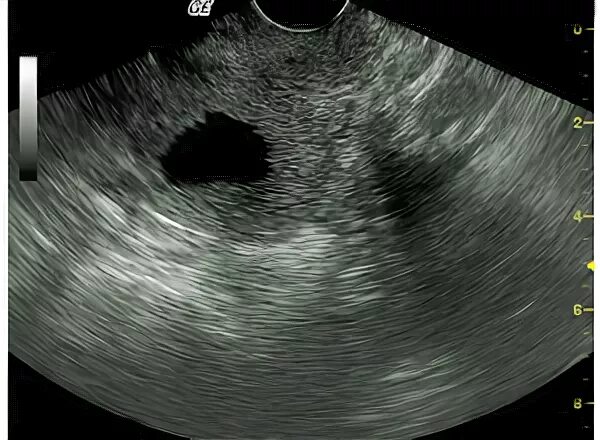

Гематометра симптомы